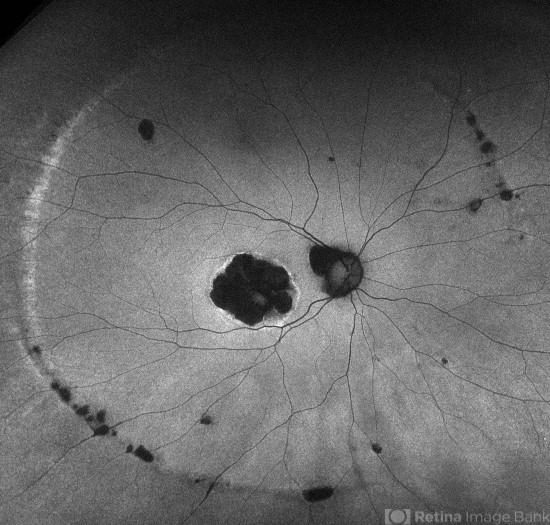

- Histoplasmosis Capsulatum Retinitis

- histoplasmosis, presumed ocular histoplasmosis syndrome (POHS)

- Autofluorescence image of a 63-year-old woman with presumed ocular histoplasmosis syndrome OD observed for change.